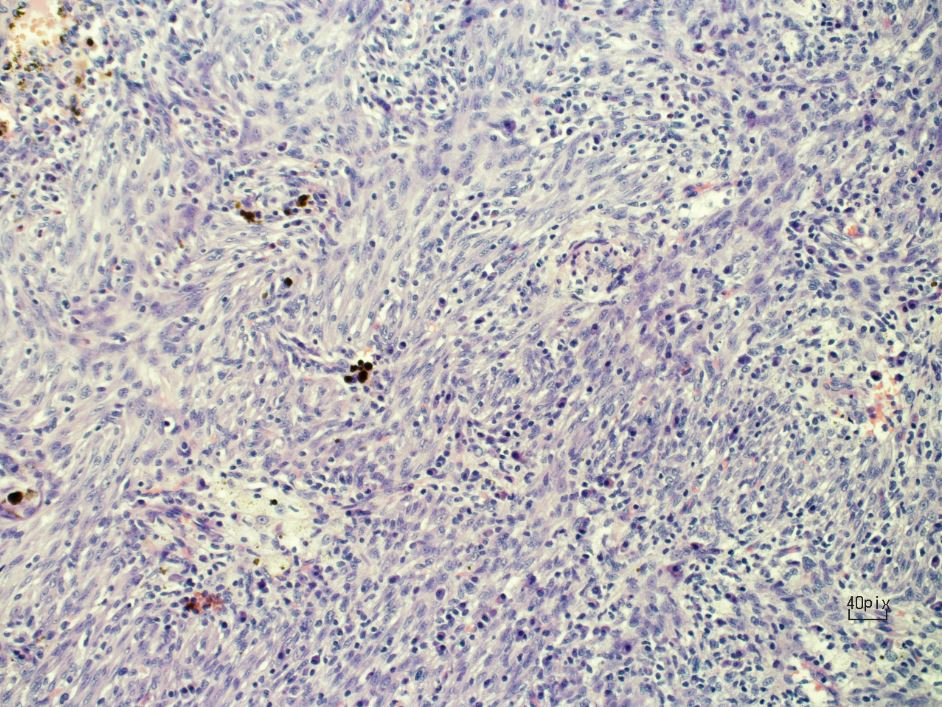

Figure 3. Bland-looking spindle cells.

Inflammatory myofibroblastic tumors (IMT) were first observed and described by Bunn in 1939, and were later named by Umiker and colleagues. IMTs are a rare type of lesion that affect different anatomical locations of the body, and they make up 0.7% of tumors in the lung, parenchyma, and bronchus (1). An IMT usually presents as a solitary nodule but can also present as a locally invasive lesion. Pathologically, IMTs are identified by a proliferation of spindle cells associated with a variably dense polymorphic infiltration of mononuclear inflammatory cells.